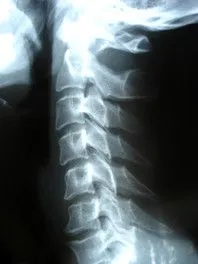

Shown above is an x-ray film of a structurally fairly normal cervical spine( neck ) with a seemingly extended( = bent backward ) 6th cervical vertebra.

Spinal examination is integral to chiropractic, and includes meticulous palpation (feeling) to identify stiff, dysfunctional or misaligned joints , that can irritate the nervous system and accelerate degenerative damage. These areas of joint dysfunction can also be found in the extremities, rib cage or cranium. The chiropractor will carefully feel the tissues and joints and record any restrictions to motion( fixations ) or tender trigger points, that may refer pain into other areas of the body. Abnormal muscle function is noted, such as tightness, weakness, or poor co-ordination of contraction, all of which may cause or contribute to abnormal strains and stresses on the joints. Posture is examined and correlated with the patient's symptoms, thus forming the basis for corrective exercises or ergonomic advice aimed at lessening stresses on the body.